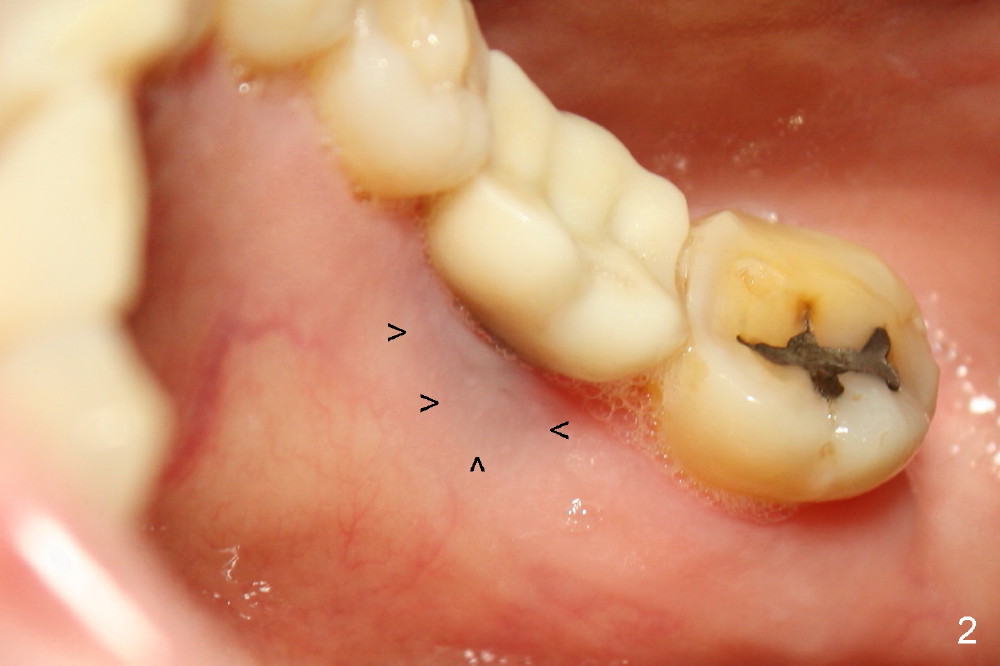

Thirteen months post bone graft via buccal approach, the patient has remained asymptomatic. There is no sign of infection buccally (Fig.1), but the lingual gingiva is erythematous (Fig.2 arrowheads) with deep pocket (Fig.3). Since the patient will be out of country for 7 months, exploration is going to be done immediately. Preop PA reveals mesial bone loss (Fig.4 M).

Upon flap reflection and granulation tissue curettage, the lingual threads are shown to be exposed with mesial bone resorption (Fig.5 <). The lingual defect is soaked with Clindamycin saturated gauzes (Fig.6 *), followed by copious irrigation, Emdogain application, bone graft and collagen dressing. The flap is sutured and covered by perio dressing.

The chronic infection with bone loss is probably due to two factors. No bone graft was placed at the time of immediate implant. The infection might come from the extraction site (due to incomplete debridement of the socket) or from a remote area: #9 endo perio lesion.